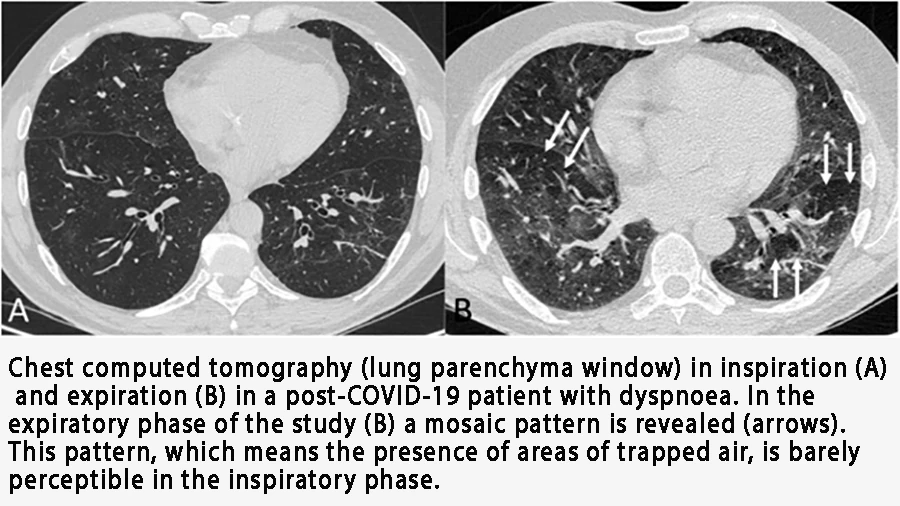

Doctors often see the aftermath on CT scans as “ground-glass opacities”—hazy areas that signal inflammation and damage.